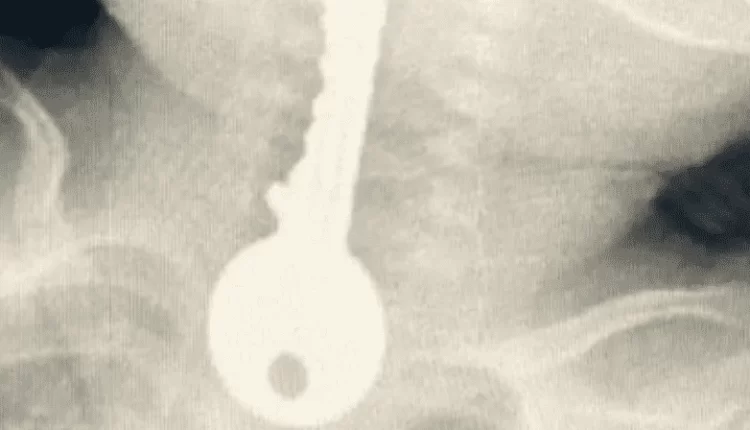

وأوضح مجمع الملك فيصل الطبي عبر حسابه في تويتر، أنه استقبل حالة طفل في وضع صحي حرج يعاني من ضيق في التنفس، مما استدعى تقديم الإسعافات الأولية وإجراء الفحوصات السريرية والإشعاعية.

وكشفت الفحوصات وجود جسم غريب على شكل مفتاح في المريء.

كما أوضح الفريق المعالج للحالة أنه تم على الفور عمل منظار عاجل واستخراج مفتاح حديدي من المريء كاد أن يودي بحياته.